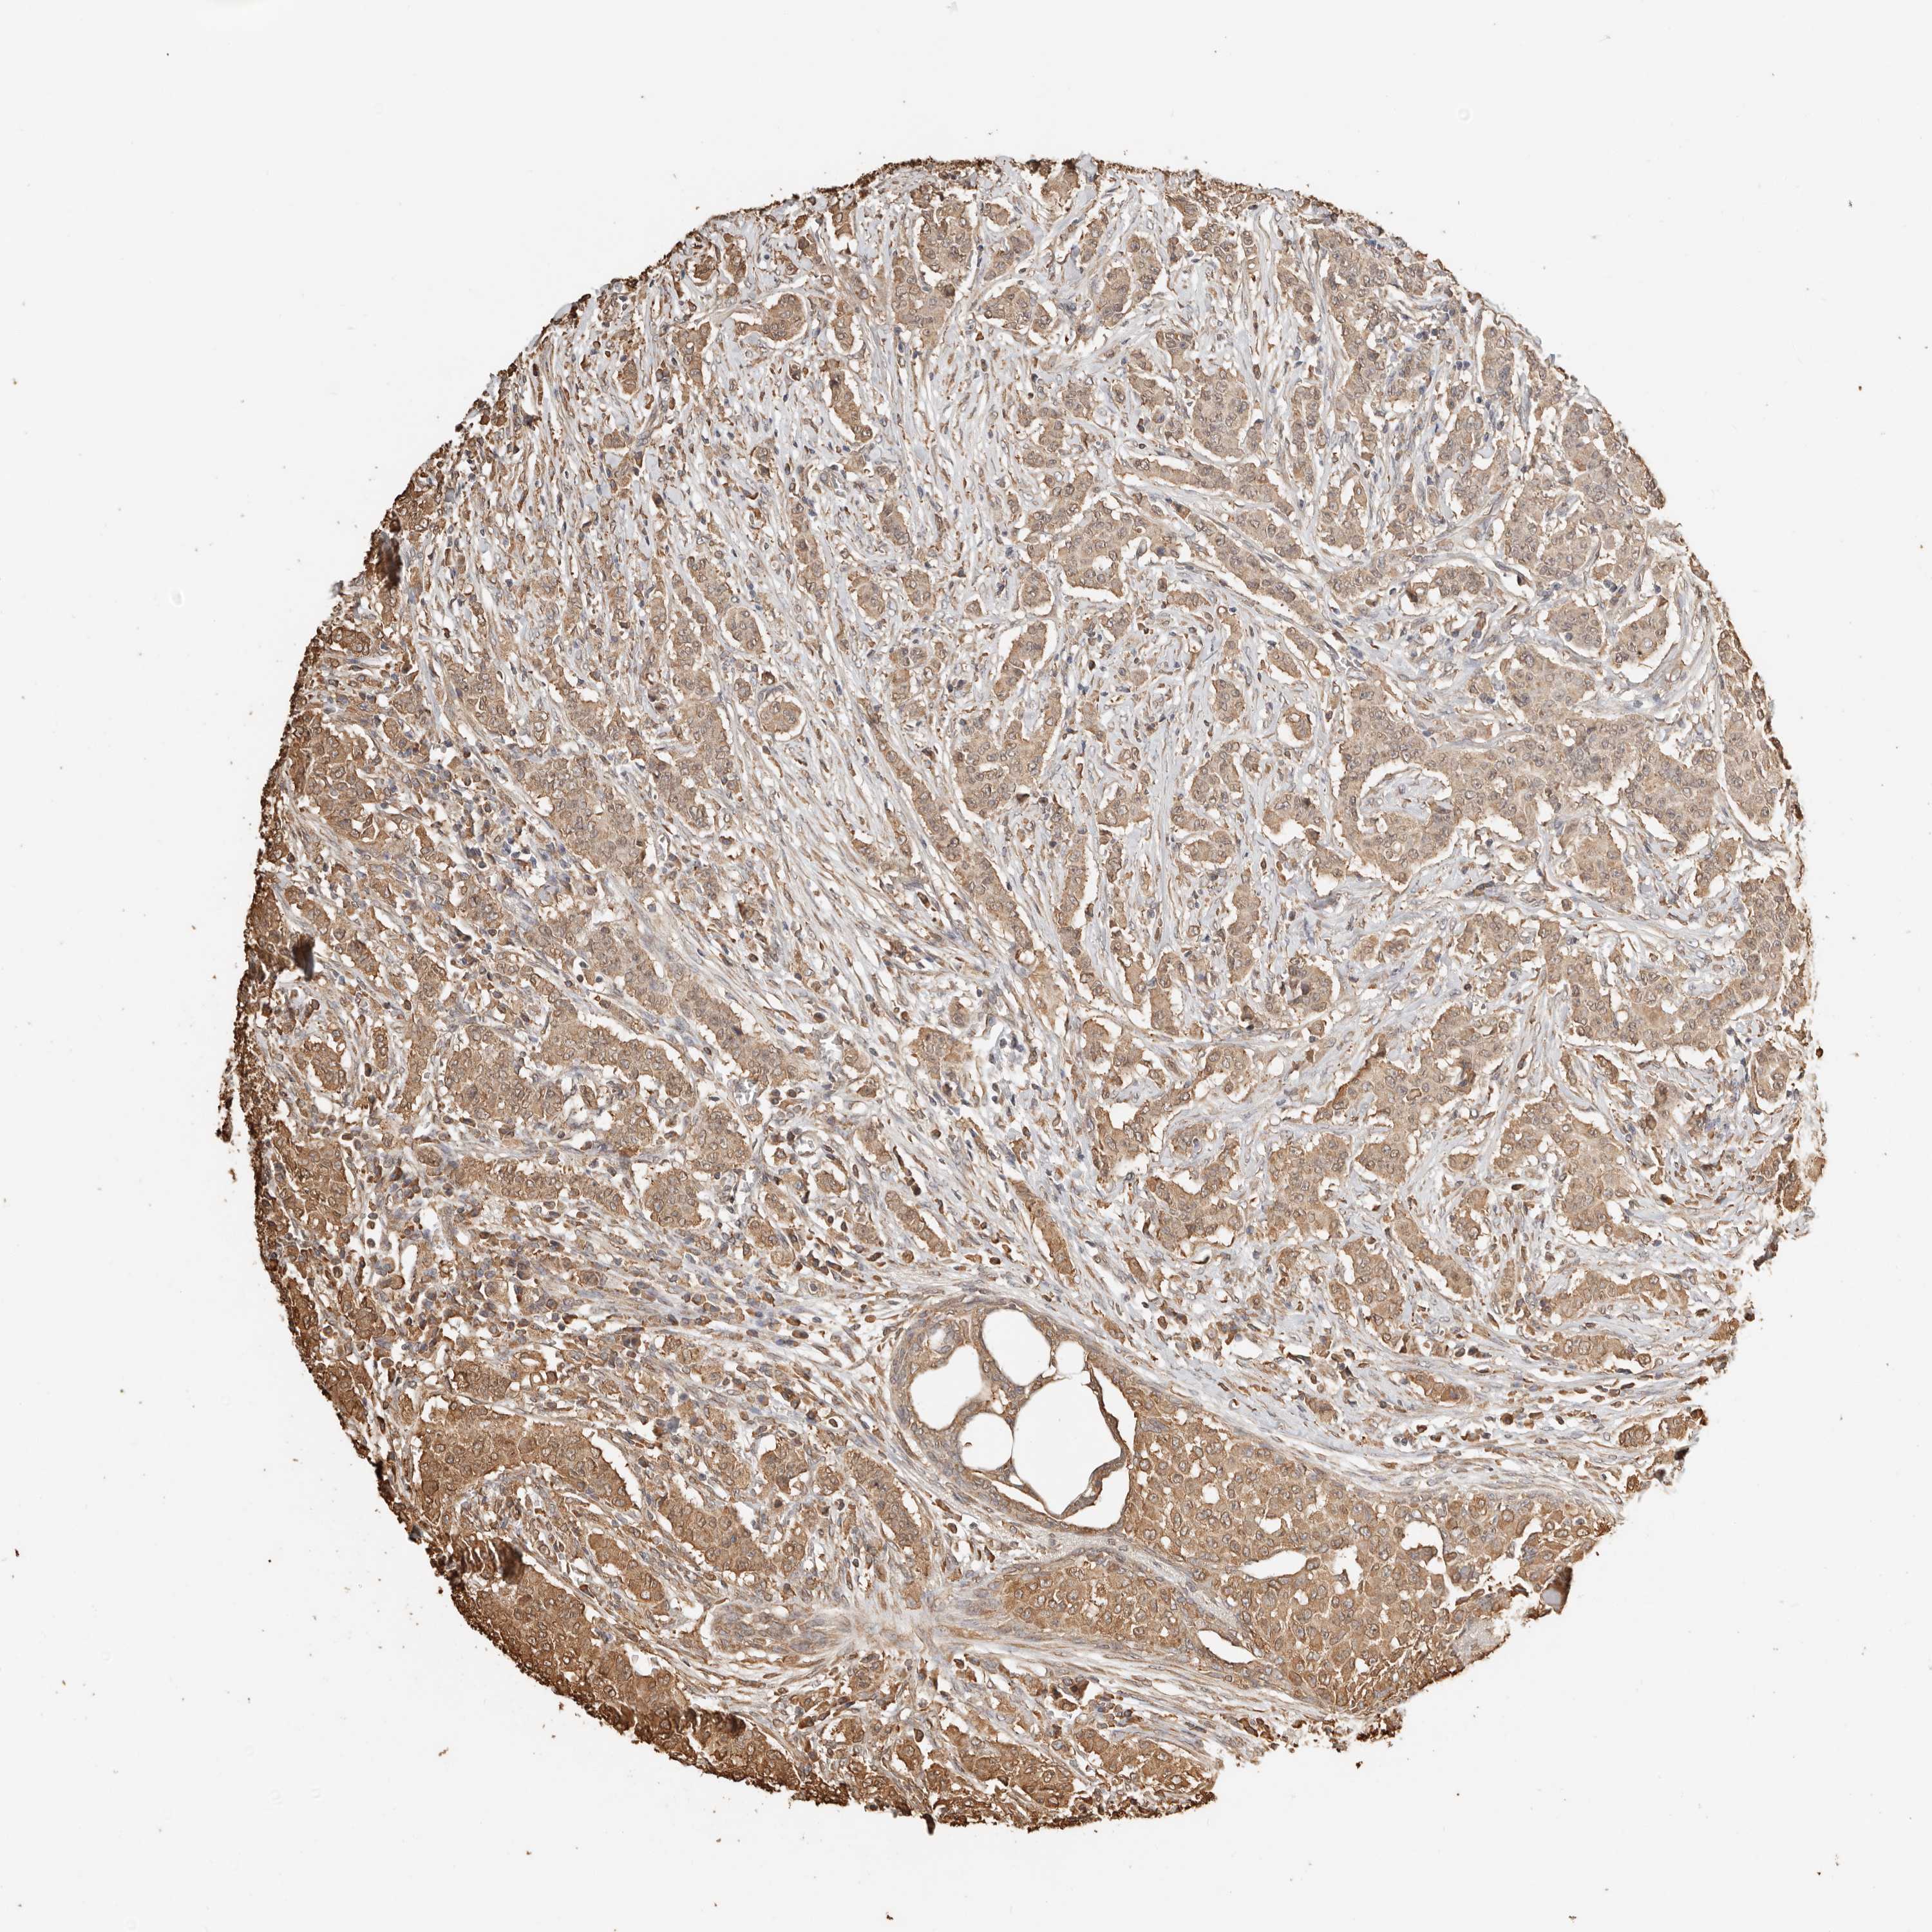

CANCER BREAST CANCER Show tissue menu

BRCA TCGA BRCA VALIDATION PROTEIN EXPRESSION